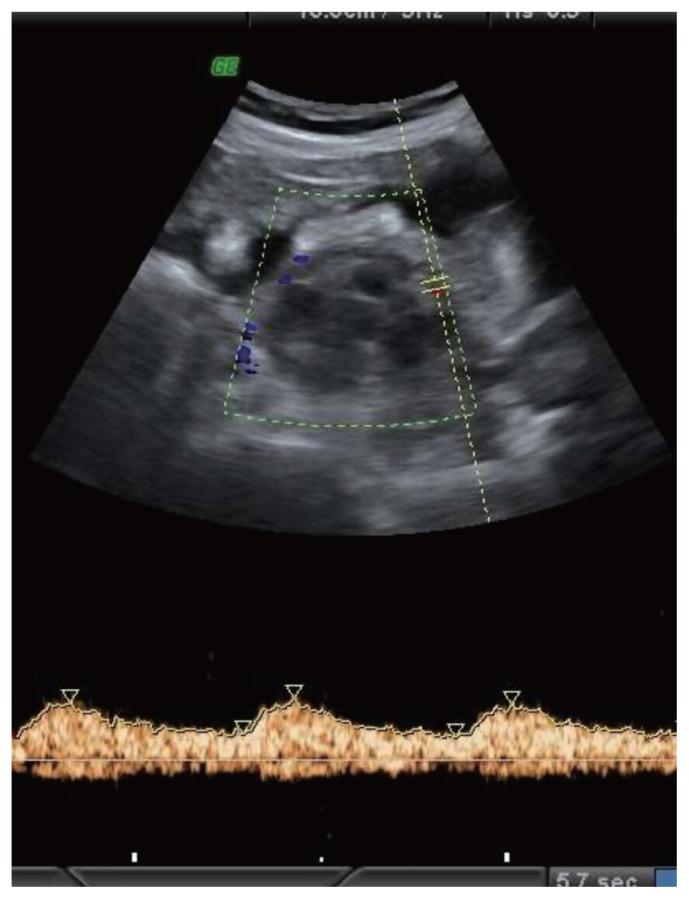

This observational longitudinal prospective analysis of 60 patients was performed over a period of 2 years (2017- 2019). The mean age of the patients was 43.75 years. Ultrasonography of ovarian masses were evaluated, and cancer antigen-125 (CA-125) levels were evaluated. Based on the IOTA classification, the B and M features of adnexal masses were studied. Color Doppler imaging was performed to evaluate the patterns of vascularity and indices.

Sixty patients with 35 benign, 23 malignant, and two borderline lesions were included in the study. In malignant lesions, 17 women (73.9%) were above the age of 45. The CA-125 cut off was ≥35 internatioal units/mL. Based on the IOTA classification, 27/35 (77.1%) benign cases, were correctly identified as benign, 6/35 (17.1%) benign cases were incorrectly identified as malignant, and two (5.7%) were found to be inconclusive. In the malignant group, 17 of the 23 patients were identified as having malignancy. Color Doppler showed three (18.8%) benign tumors had a pulsatality index (PI) of <0.8 and 21 malignant tumors had a PI of <0.8. Four benign tumors had an resistive index (RI) of <0.6 and 100% of malignant tumors had an RI <0.6.

方法

本研究纳入了60例患者,其中35例为良性病变,23例为恶性病变,2例为交界性病变。在恶性病变中,17名女性(73.9%)年龄超过45岁。CA - 125临界值为≥35国际单位/毫升。基于IOTA分类,35例良性病例中有27例(77.1%)被正确鉴定为良性,35例良性病例中有6例(17.1%)被错误鉴定为恶性,2例(5.7%)结果不明确。在恶性组中,23例患者中有17例被鉴定为患有恶性肿瘤。彩色多普勒显示3例(18.8%)良性肿瘤的搏动指数(PI)<0.8,21例恶性肿瘤的PI<0.8。4例良性肿瘤的阻力指数(RI)<0.6,100%的恶性肿瘤RI<0.6。